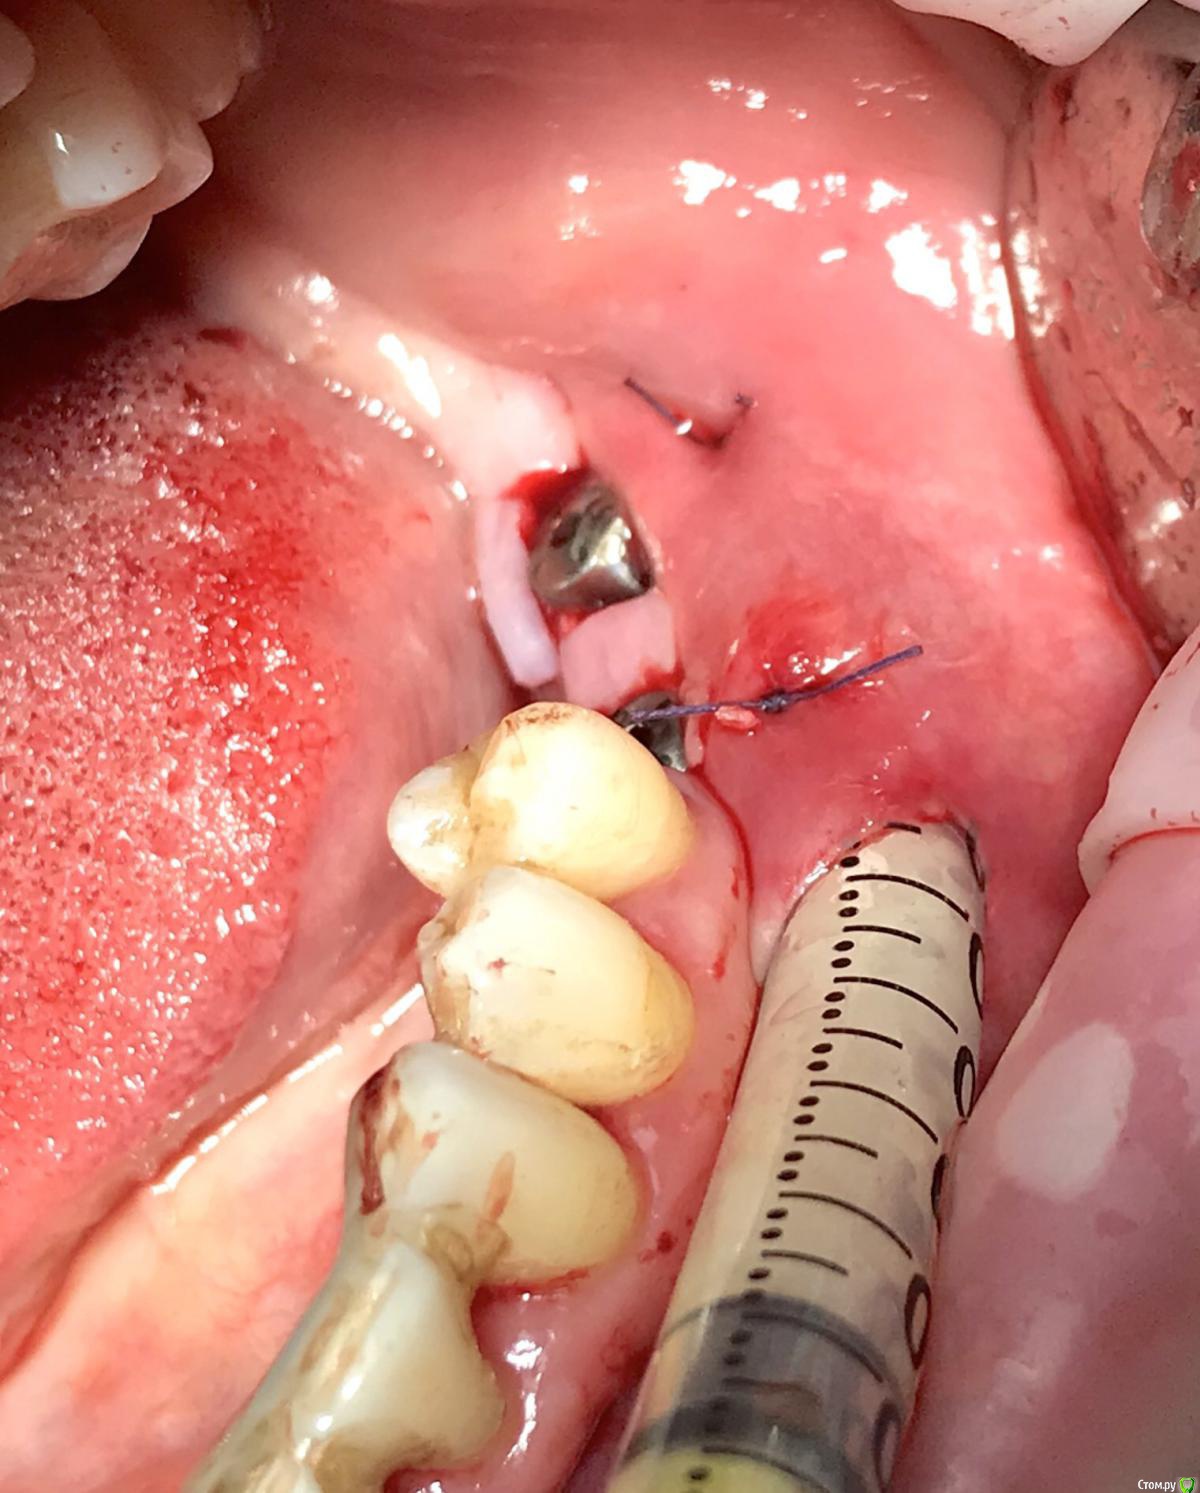

колесников Опубликовано 16 декабря, 2018 Автор Поделиться Опубликовано 16 декабря, 2018 (изменено) Поставлена задача:возместить дефект зубного ряда. Бюджет ограничен. Как видно по кт,для имплантации нет сложностей. Импланты Астра 4.0,поставлены с заглублением в оптимальной позиции. Дефицит прикреплённой слизистой вестибулярно у шеек имплантов возмещён роллом с гребня. Можно было этим ограничится. Однако при протезировании дефицит объема тканей будет очевиден. Роллы фиксированы к подвижной и тонкой слизистой,результат сомнительный,тк нет стабильности. Щечный тяж и скат гребня неминуемо приведут к рецесси слизистой у шеек имплантов. Можно было восстановить объём гребня при помощи нкр,затем лоскут с неба ( 1 год лечения). Или хотябы подсадить сст пожирнее.а потом асл (6мес),на первое время хватило бы. Но . Бюджет ограничен. Сроки тоже. Слово «костная пластика» вызывает панику. Новая задача: минимизировать вмешательства,убрать тяжи,создать объём,небо не трогаем. Проводим тоннельный графтинг. Получаем объём,поднимаем ткани и тяжи не тянут. Роллы получают покой ,стабильность и созревают в кратчайшие сроки. Графт поднадкостнично. Графт стабилен. Графт пропитался кровью,графт созревает. Результат быстрый. Дискомфорта 0. Затраты минимальные. Срок жизни такой пластики ни чем отличается от любой другой,в конечном итоге тает все. Если не стимулировать. Изменено 16 декабря, 2018 пользователем колесников 1 Ссылка на комментарий

колесников Опубликовано 17 декабря, 2018 Автор Поделиться Опубликовано 17 декабря, 2018 Можно и так и так. Удобнее с имплантации начинать Ссылка на комментарий

колесников Опубликовано 19 декабря, 2018 Автор Поделиться Опубликовано 19 декабря, 2018 Чтобы ролл зафиксировать . Ссылка на комментарий